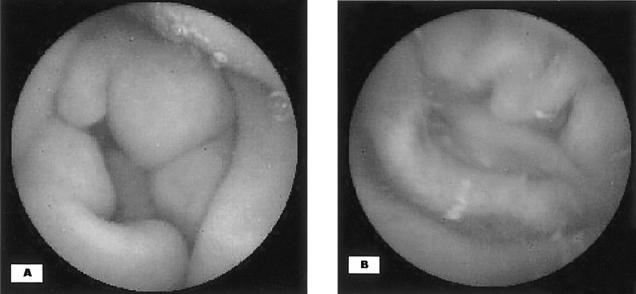

Eosinophilic enteritis presenting as intussusception in adult.

Eosinophilic gastroenteritis is defined as a disorder that selectively affects the gastrointestinal tract with eosinophil-rich inflammation in the absence of any known causes for eosinophilia. The clinical manifestations vary according to the site of the eosinophilic infiltrated layer of the bowel wall. Eosinophilic enteritis presenting as intussusception in adult has not been previously reported in the literature. Especially, making the diagnosis of intussusception in adults is often difficult due to the variable clinical findings. In our case, the correct diagnosis of intussusception due to eosinophilic enteritis was arrived at rather easily based on the ultrasonography and endoscopic biopsy. The patient was treated with oral prednisolone at 30 mg/day for 7 days, and then the drug was tapered off for 2 months; we didn't perform surgery. He has been asymptomatic for about 1 year after discharge without disease recurrence.